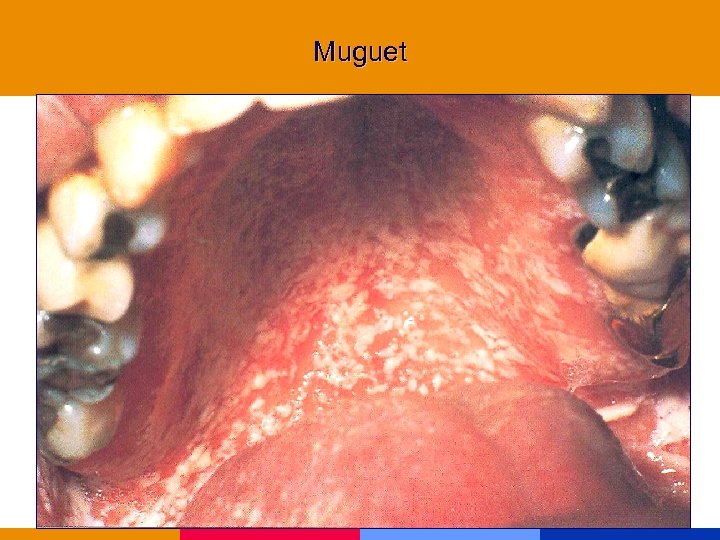

Muguet

Muguet

Muguet

Muguet